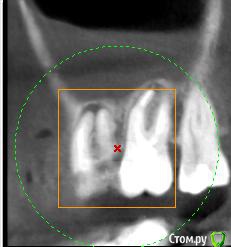

Helen22 Опубликовано 12 декабря, 2015 Автор Поделиться Опубликовано 12 декабря, 2015 Спасибо за оперативные ответы) промучилась с этим КТ(оно действительно для ЛОРа), но не смогла ничего в нем сделать.Сделала сегодня КТ 16, 17, 18 вот принт- скрины, правда не знаю насколько они будут информативными.... Ссылка на комментарий